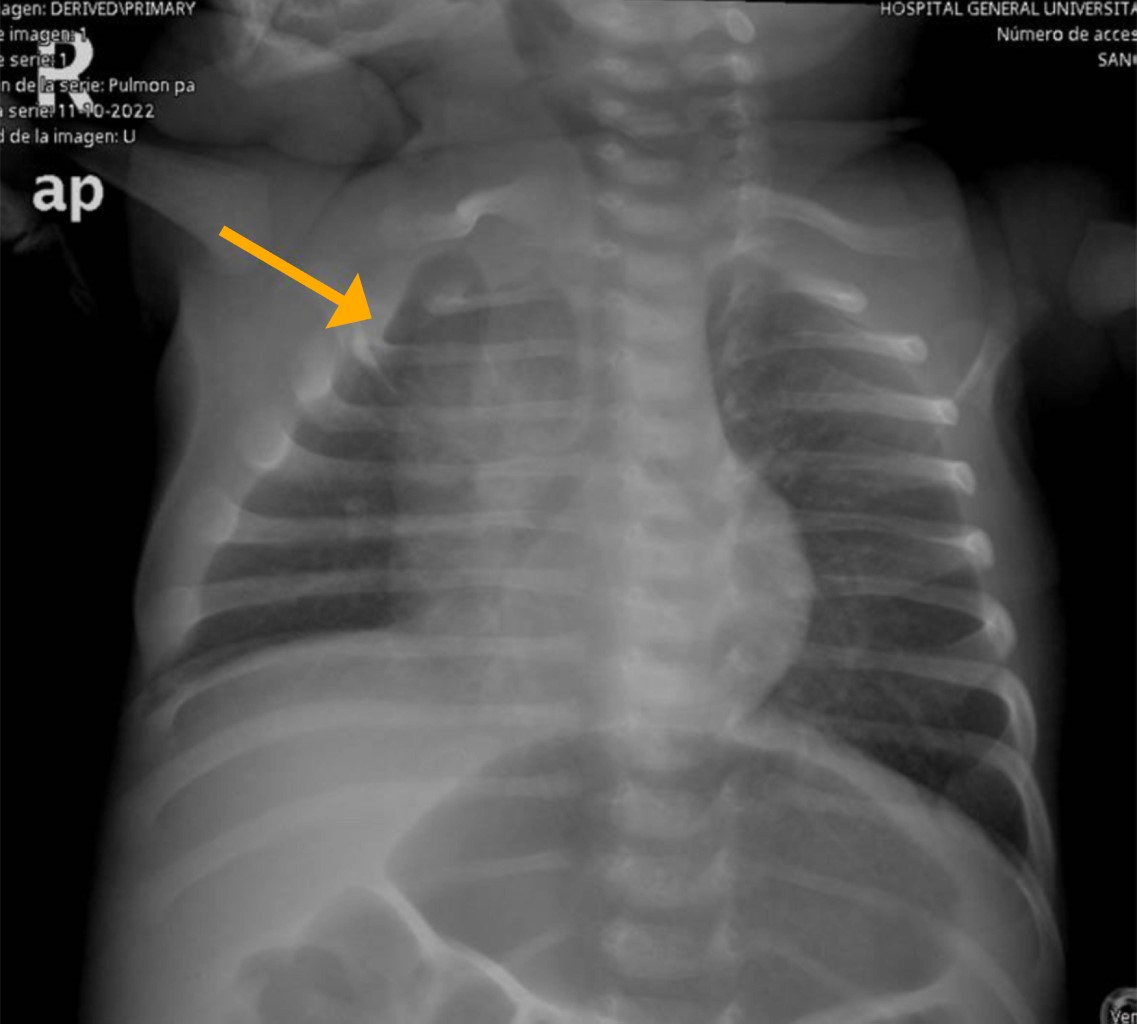

A la exploración, se encontraba asintomático, con peso de 3,950 g y talla 50 cm. No mostraba signos de fatiga durante la alimentación. Signos vitales normales (FC 141 lpm, TA 86/52 mmHg) y pulsos periféricos palpables en las cuatro extremidades. No se identificaron rasgos dismórficos, tampoco alguna masa o megalia abdominal. En precordio se auscultaba soplo sistólico II/VI en borde paraesternal izquierdo. El ECG mostró signos de crecimiento de cavidades derechas, sin otras alteraciones (Figura 1). La radiografía de tórax era normal, sin cardiomegalia (Figura 2).

Figura 2